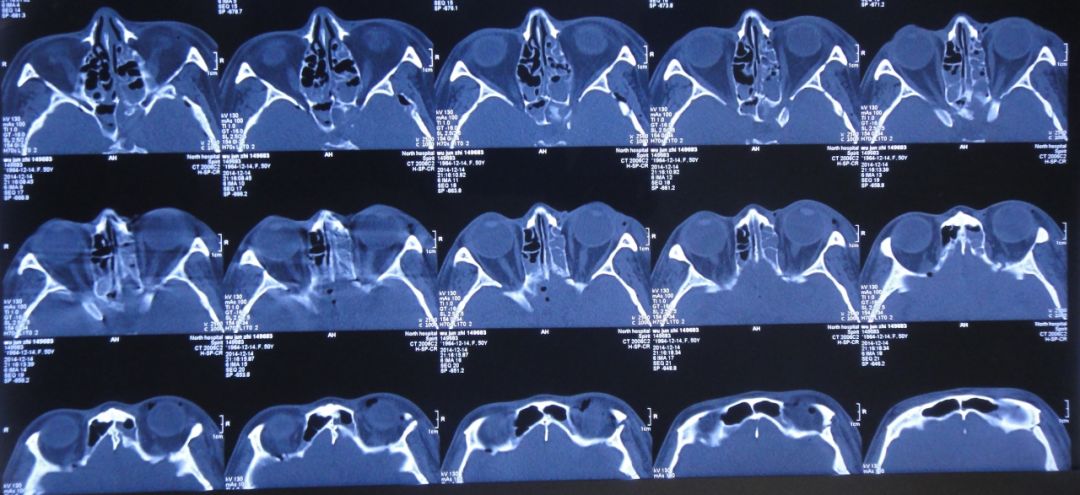

患者女,50岁,安徽省淮北市人。2014年12月14日,患者因高处坠落伤(2米左右)伤及头胸部及四肢,致昏迷,左耳、左鼻流血性液体,急诊前往安徽省淮南市潘集区某医院急查头CT显示左额叶脑挫伤、左侧颞骨凹陷性骨折、脑肿胀、颅内积气(图1);眼眶CT显示双侧眼眶内侧壁骨折(图2);胸部CT显示左侧肋骨骨折伴肺挫伤;右上肢X片显示右桡骨远端粉碎性骨折;左肩部X片显示左侧锁骨骨折。立即给予住院,保守治疗。

图2:2014年12月14日眼眶CT:双侧眼眶内侧壁骨折